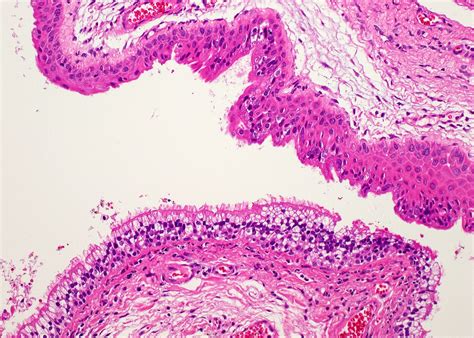

The exact cause of a Cyst Thyroglossal Duct is not fully understood, but it is believed to be related to the incomplete obliteration of the thyroglossal duct during embryonic development. This can lead to the formation of a cyst, which is a fluid-filled sac. The cyst can vary in size and may become infected or inflamed, leading to discomfort and other symptoms.